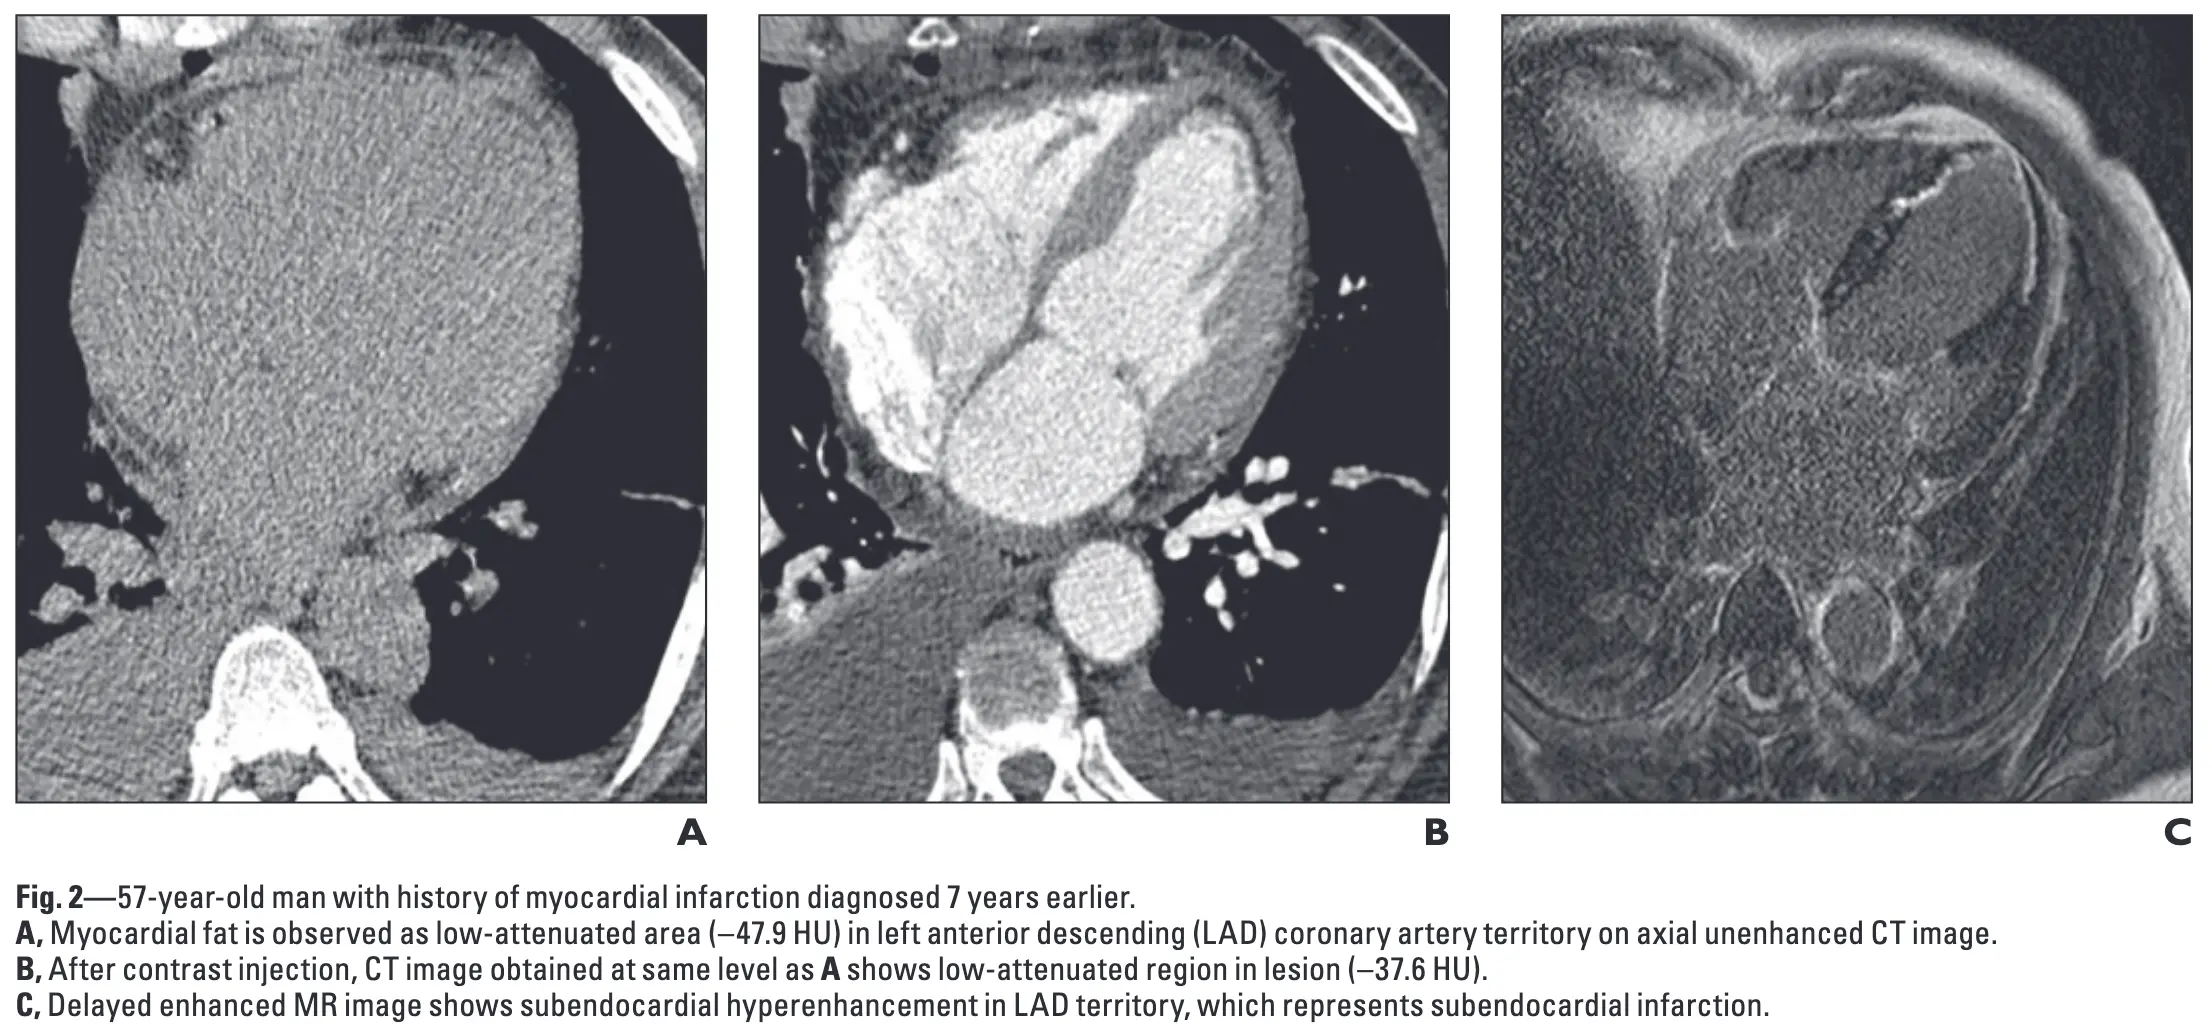

Ischemia may appear as subendocardial hypoattenuation, fatty metaplasia or calcification

- Figure source: 1

-

Ahn SS, Kim YJ, Hur J, Lee HJ, Kim TH, Choe KO, Choi BW. CT detection of subendocardial fat in myocardial infarction. AJR Am J Roentgenol. 2009 Feb;192(2):532-7. doi: 10.2214/AJR.08.1608. PMID: 19155421. ↩